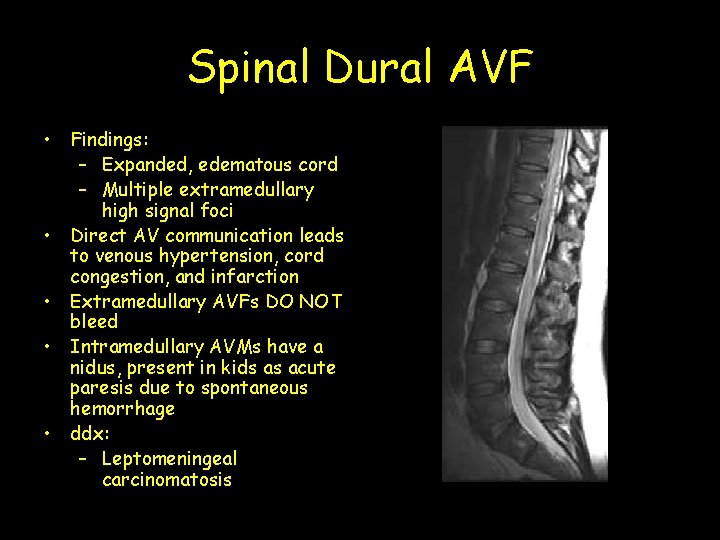

Spinal Dural AVF • Findings: – Expanded, edematous cord – Multiple extramedullary high signal foci • Direct AV communication leads to venous hypertension, cord congestion, and infarction • Extramedullary AVFs DO NOT bleed • Intramedullary AVMs have a nidus, present in kids as acute paresis due to spontaneous hemorrhage • ddx: – Leptomeningeal carcinomatosis